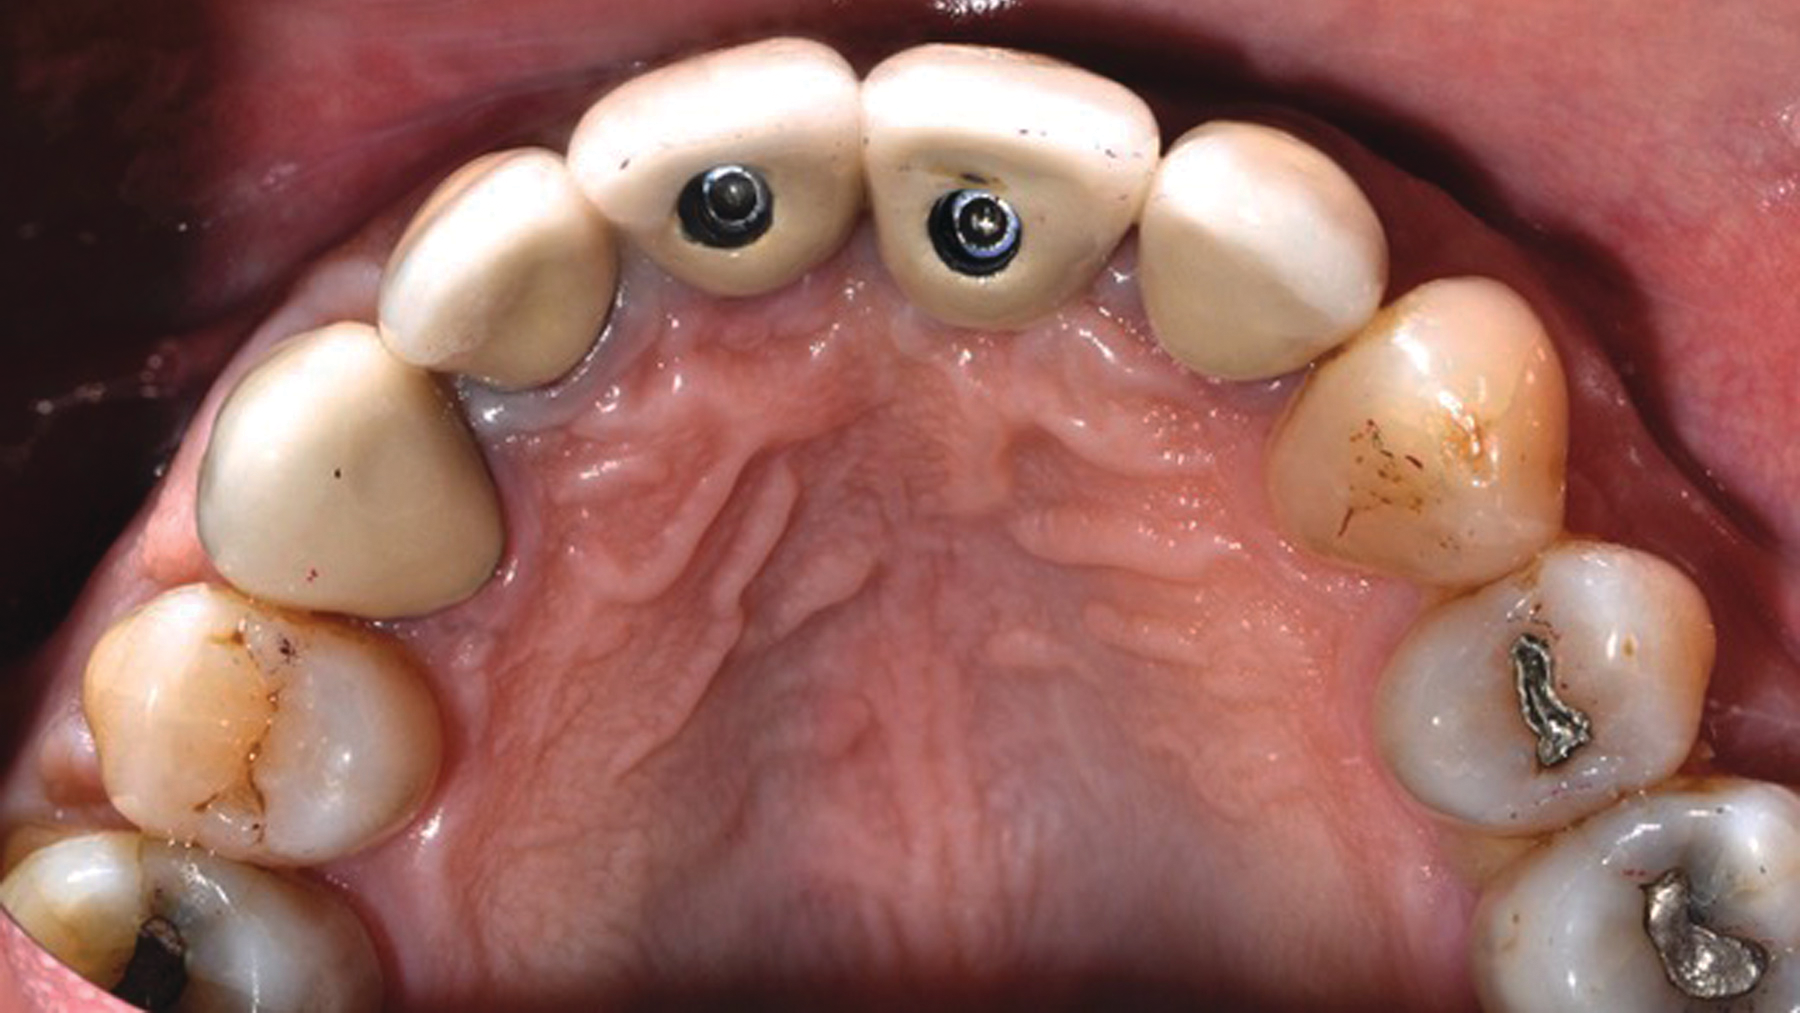

Author Gary Morris, DDS, tracked the paradigm shift from cement- to screw-retained implant restorations in his clinical prosthodontic practice. This was directly related to the introduction of angled implants (Co-Axis Implants, Southern Implants; figure 1). Co-Axis Implants were designed with angle offsetsGrowth of simultaneous extraction and molar implant placement